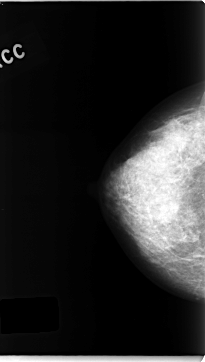

C_0142_1.RIGHT_CC

RIGHT_CC LINES 4704 PIXELS_PER_LINE 2664 BITS_PER_PIXEL 12 RESOLUTION 50 NON_OVERLAY